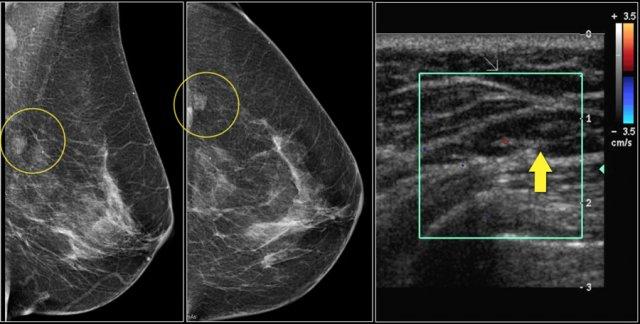

Lưu ý sự biến dạng cấu trúc vú bình thường trên tư thế chếch (vòng tròn vàng) và tư thế phóng đại.

Bệnh nhân đã được phẫu thuật cắt bỏ và chỉ tìm thấy mô sẹo trong bệnh phẩm.

Đây là ví dụ về bất đối xứng khu trú thấy trên tư thế MLO và CC.

Chụp ép khu trú và siêu âm không phát hiện khối nào.